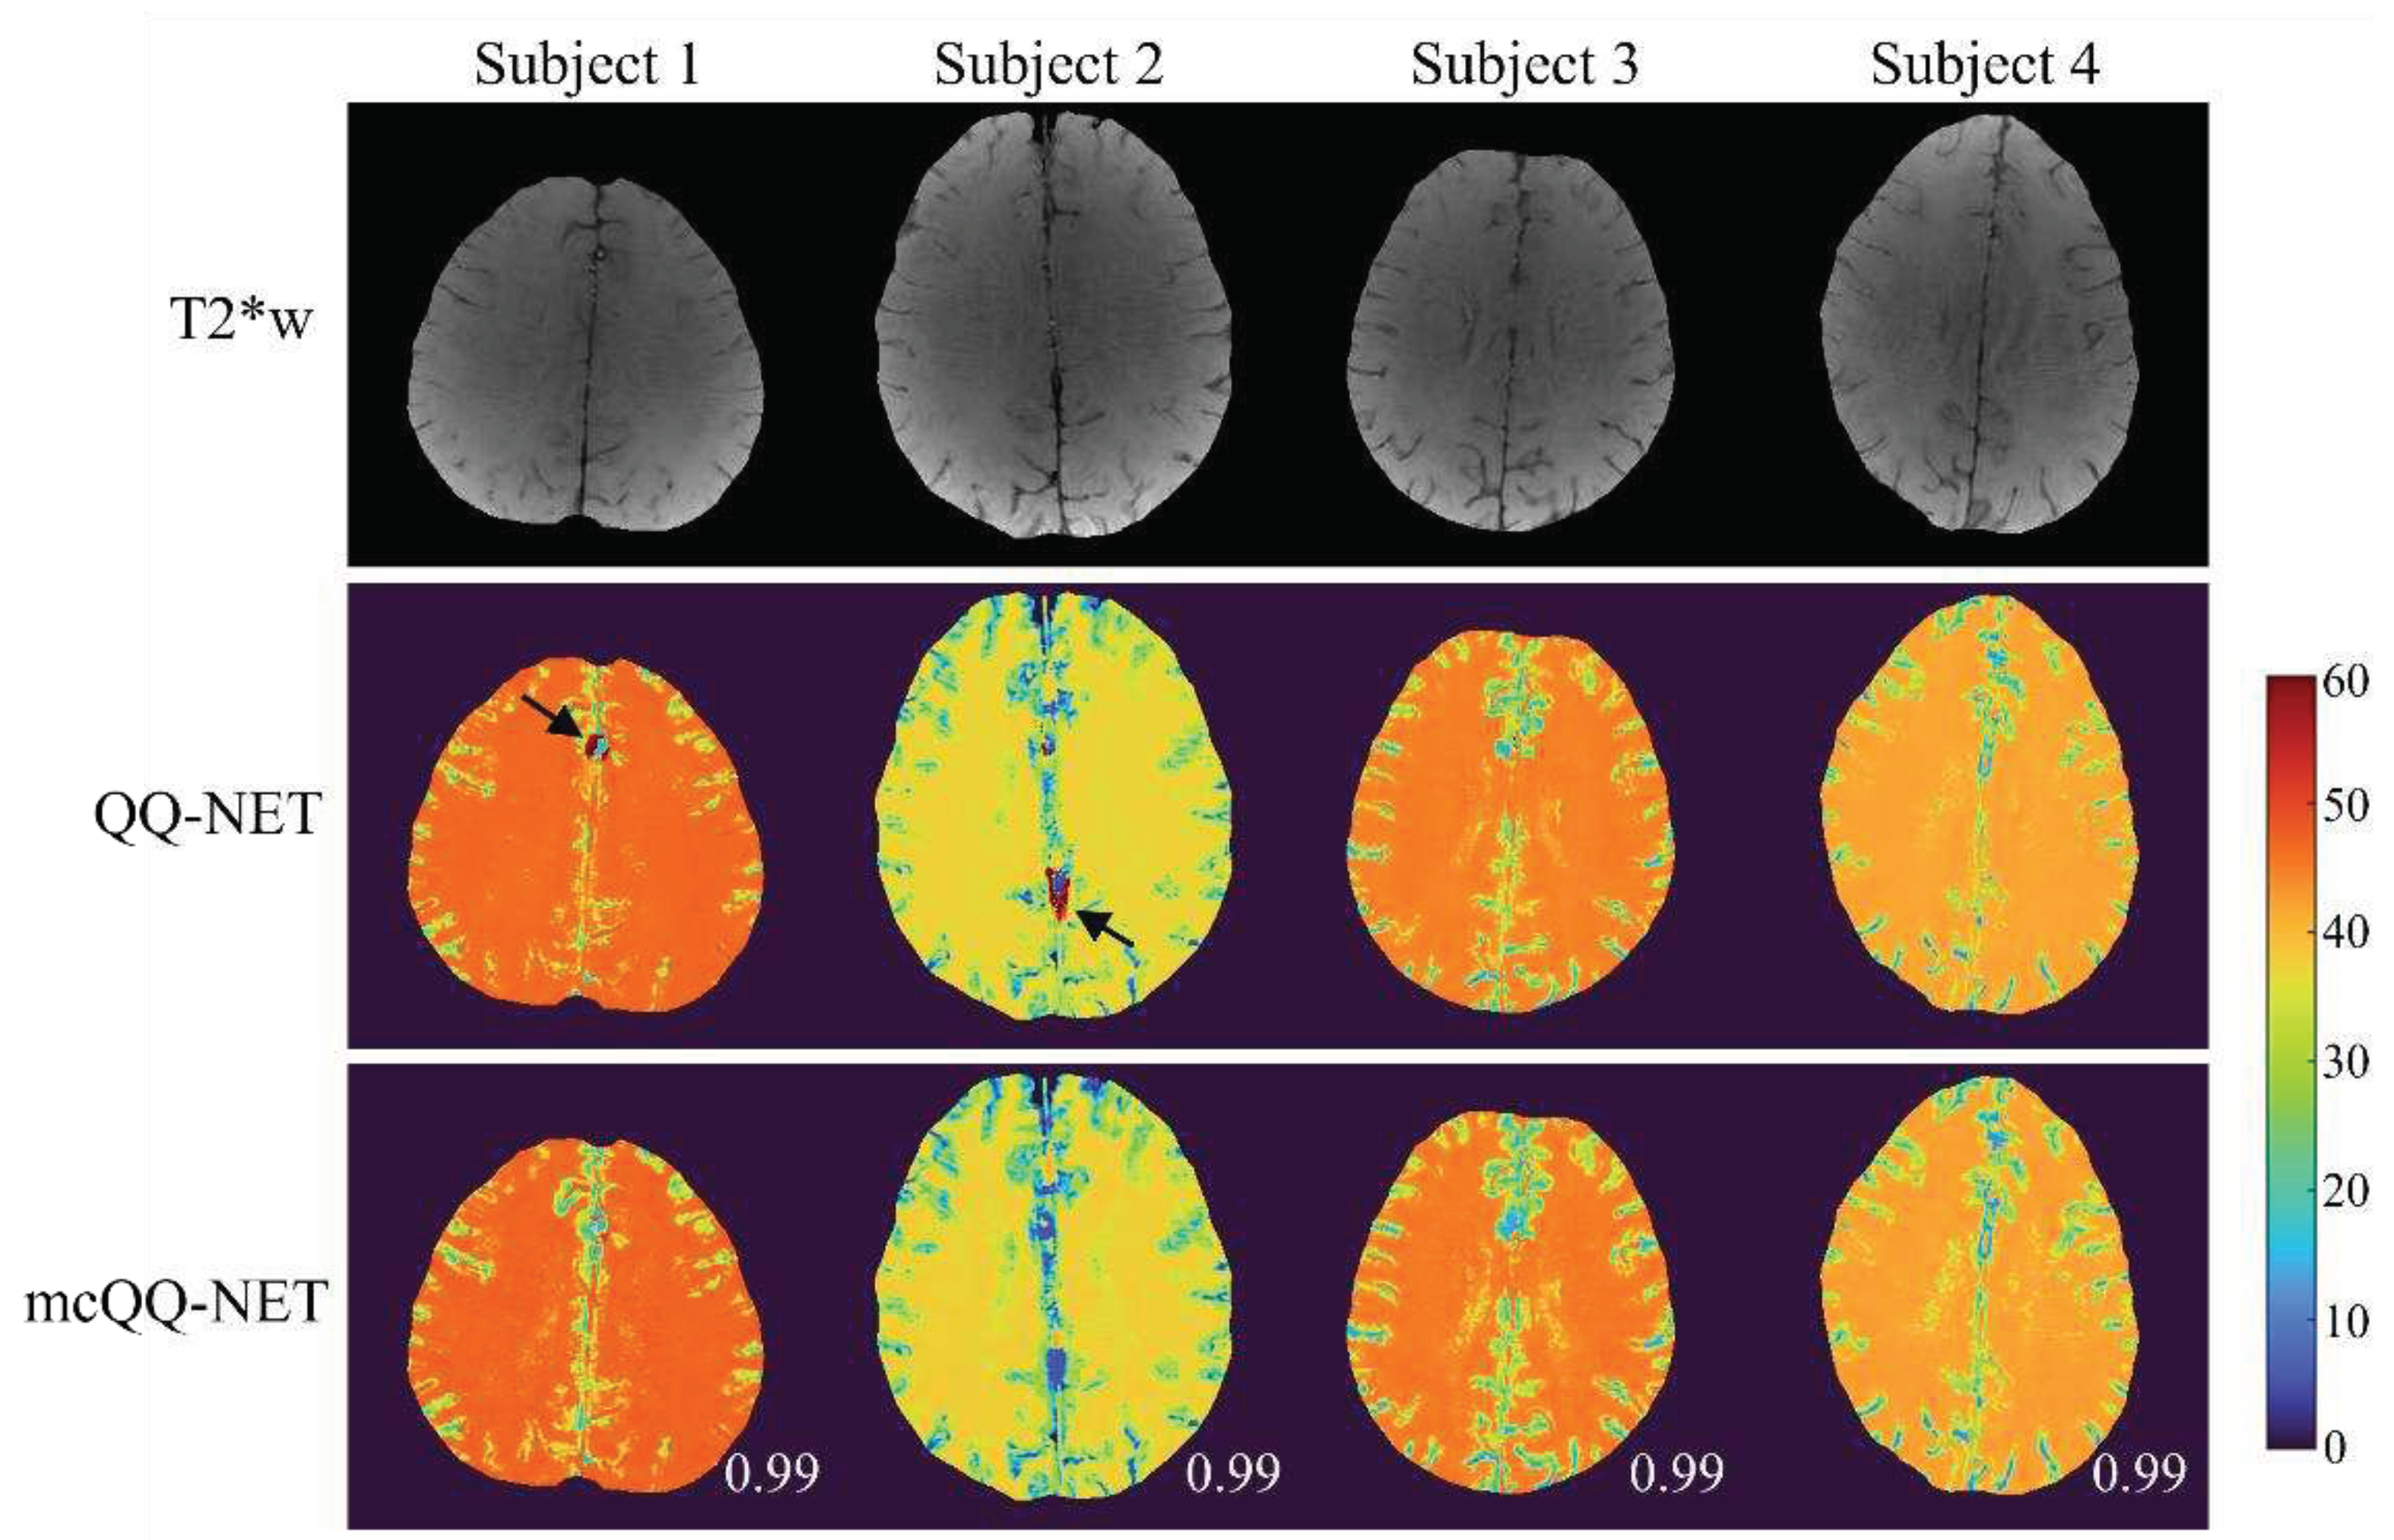

- Cho, J.; Zhang, J.; Spincemaille, P.; Zhang, H.; Hubertus, S.; Wen, Y.; Jafari, R.; Zhang, S.; Nguyen, T.D.; Dimov, A.V.; et al. QQ-NET - using deep learning to solve quantitative susceptibility mapping and quantitative blood oxygen level dependent magnitude (QSM+qBOLD or QQ) based oxygen extraction fraction (OEF) mapping. Magn Reson Med 2021. [Google Scholar] [CrossRef]